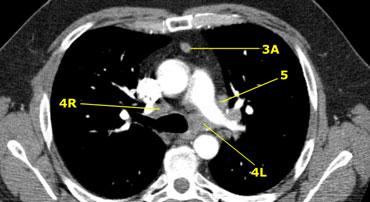

Bên trái là hình ảnh ngay trên mức thân động mạch phổi, cho thấy các hạch cạnh khí quản dưới bên trái và bên phải.

Ngoài ra còn có các hạch nhóm 3 và nhóm 5.

Bên trái là hình ảnh ở mức phần dưới khí quản, ngay trên carina.

Bên trái khí quản là các hạch 4L.

Lưu ý rằng các hạch 4L này nằm giữa thân động mạch phổi và động mạch chủ, nhưng không nằm trong cửa sổ phế động mạch, vì chúng nằm ở phía trong dây chằng động mạch.

Hạch nằm bên ngoài thân động mạch phổi là hạch nhóm 5.

4L. Hạch cạnh khí quản dưới bên trái

Hạch nhóm 4L là các hạch cạnh khí quản dưới nằm bên trái bờ trái của khí quản, giữa đường nằm ngang tiếp tuyến với bờ trên quai động mạch chủ và đường tiếp tuyến với bờ trên động mạch phổi trái.

Nhóm này bao gồm các hạch cạnh khí quản nằm ở phía trong dây chằng động mạch.

Hạch nhóm 5 (cửa sổ phế động mạch) nằm ở phía ngoài dây chằng động mạch.

5. Dưới động mạch chủ

Các hạch này nằm trong cửa sổ phế động mạch (AP window), ở phía ngoài dây chằng động mạch.

Các hạch này không nằm giữa động mạch chủ và thân động mạch phổi mà nằm ở phía ngoài các mạch máu này.

5. Hạch dưới động mạch chủ

Hạch dưới động mạch chủ hay hạch cửa sổ phế động mạch nằm ở phía ngoài dây chằng động mạch hoặc động mạch chủ hoặc động mạch phổi trái, ở đoạn gần trước nhánh đầu tiên của động mạch phổi trái, và nằm trong bao màng phổi trung thất.